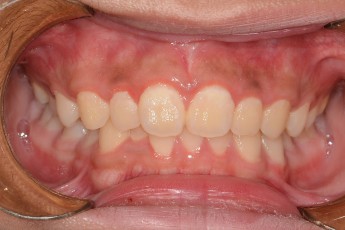

Before

After